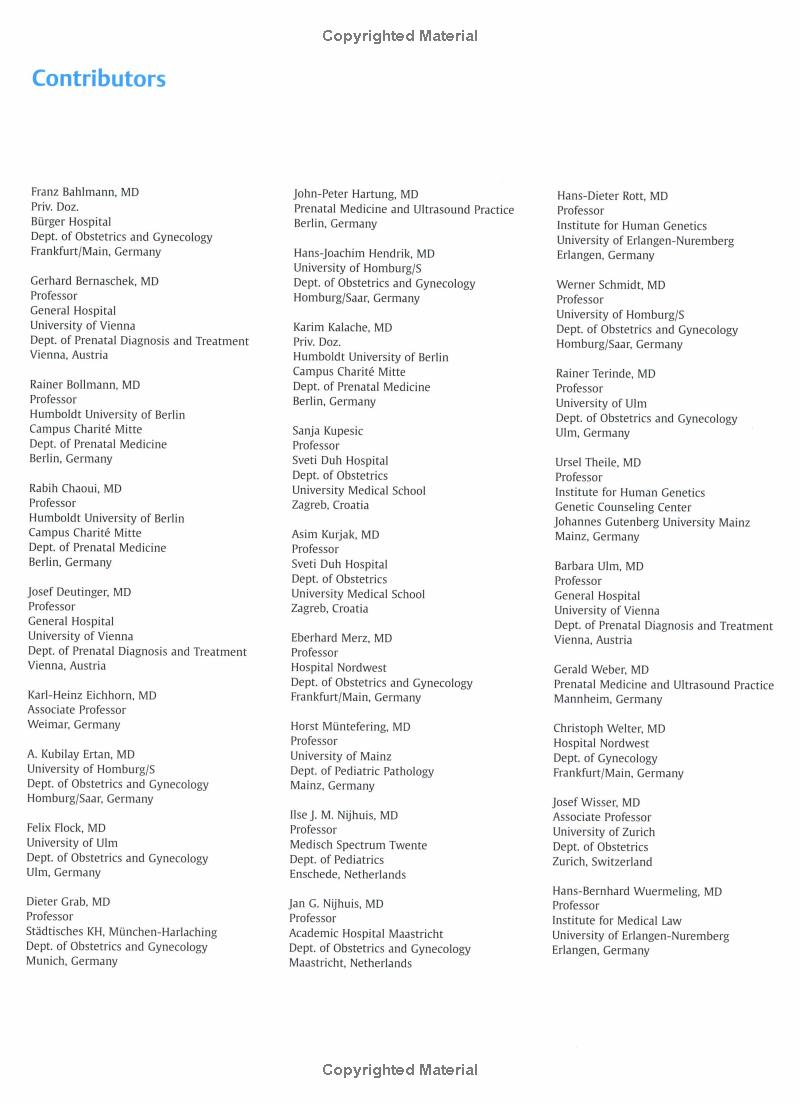

Ultrasound in Obstetrics and Gynecology Volume 1 Obstetrics Textbook and Atlas Obstetrics v. 1 2nd Edition